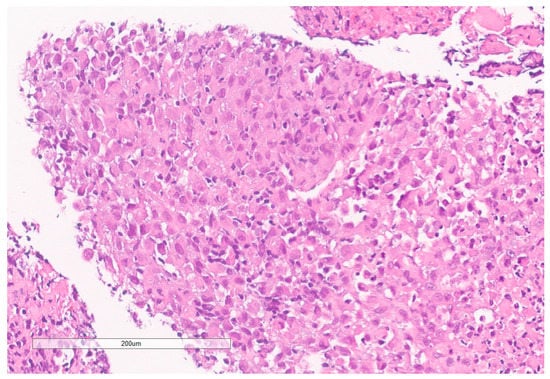

The biopsy of right kidney demonstrated mostly fibrinous material with small fragments of renal parenchyma with interstitial chronic inflammation and no definite tumor. The biopsy of a retroperitoneal lymph node showed high grade tumor composed of discohesive rhabdoid cells with highly atypical nuclei and eosinophilic cytoplasm involving lymphoid tissue with areas of necrosis and neutrophilic inflammation with necrosis and limited viable tumor cells (Figure 7). By immunohistochemistry, the cells were positive for pankeratin (Figure 8) and PAX8 (Figure 9) and negative for CK7, CK20, GATA3, CDX2, TTF1, CAIX, ERG, S100, CD34, CD30, SMA, desmin, OCT3/4 and CD163. The tumor cells showed diffuse loss of SMARCB1/INI-1 (Figure 10). The INI-1 was reviewed by several experienced pathologists that interpreted the stain as negative. While there is some background cytoplasmic and nuclear staining in the entire specimen, the norm is to compare staining with the adjacent internal positive control. Given that, in this case, the lymphocytes stained strongly positive for INI-1, it was appropriate to interpret this is as a negative stain in this context. As evidenced by the high-power image, the staining appears to be of a background variety and limited to the cytoplasm, in which the nuclei remain negative. Hence, this is interpreted as a negative stain.

Figure 7. High grade carcinoma with necrosis; tumor cells have a rhabdoid morphology.